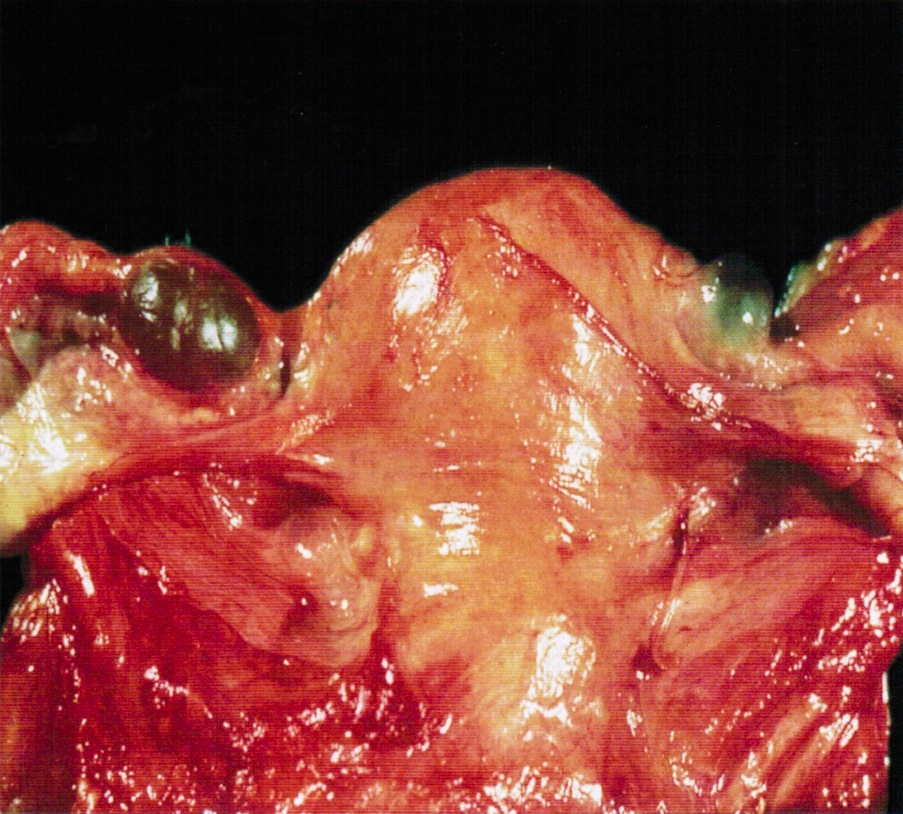

Gross description

- Firm, nodular swellings of the fallopian tube, ranging in size up to 2 cm in greatest dimension (Br J Radiol 2021;94:20201386)

- May be unilateral or bilateral

- Smooth, intact serosal covering

- Cross section of the nodules reveal gray, yellow or brown tissue punctuated by small cysts that surround the original tubal lumen (StatPearls: Salpingitis Isthmica Nodosa [Accessed 22 June 2023])

- Nodosity of the isthmus may give the uterus a horned appearance

Gross images